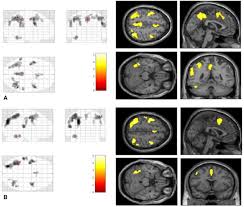

Structural And Functional Footprint Of Visual Snow Syndrome Brain Oxford Academic

Structural And Functional Footprint Of Visual Snow Syndrome Brain Oxford Academic from f1.media.brightcove.com